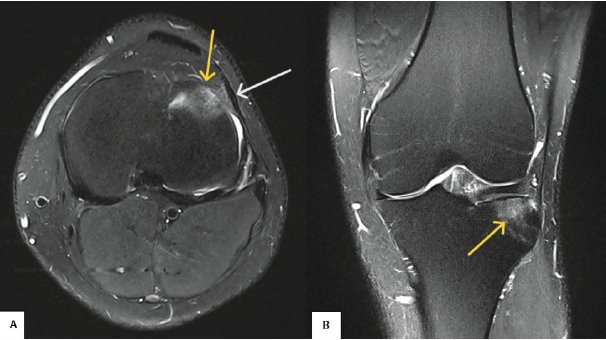

There was no significant finding on plain X-ray of the left knee in orthogonal views. MRI of the left knee demonstrated linear thickening of the lateral patellar retinaculum extending from the inferolateral patellar border to the lateral aspect of the proximal tibia (near tibial tubercle), corresponding to the LPTL. The LPTL appeared thickened in comparison to its medial counterpart. Associated bone marrow edema was noted at the anterolateral tibial cortex adjacent to Gerdy’s tubercle, precisely at the site of ligamentous attachment. On MRI, the marrow edema was seen as a hyperintense signal on T2-weighted (Fig. 1) and proton density fat-suppressed (PDFS) sequences (Fig. 2), with corresponding hypointensity on T1-weighted images. The signal alteration was limited to the subcortical marrow without evidence of cortical breach, fracture line, or intraosseous cyst formation. These findings are consistent with enthesopathic stress-related changes at the tibial insertion of the LPTL and correlated well with the patient’s localized pain and tenderness. The cruciate ligaments, collateral ligaments, menisci, and articular cartilage were all intact, and no joint effusion was observed.

Figure 2: Axial (a) and coronal (b) proton density fat-suppressed images of the left knee joint show marrow edema (yellow arrow) at the anterolateral aspect of the tibial plateau (Gerdy’s tubercle) near tibial insertion site of lateral patellar tibial ligament (white arrow).